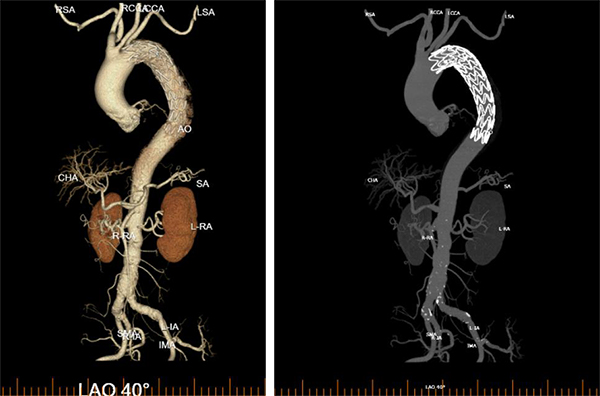

李阿姨今年79岁了,2026年2月27日一早起床,突然觉得胸背剧烈疼痛难忍,自己觉得可能心脏出问题了,家人赶紧拨打120送到东方医院急诊科。急诊科副主任张志辰接诊后依据丰富的临床经验初步考虑存在主动脉夹层可能,遂立即进行胸腹CT检查,并完成急查主动脉CTA,确诊患者为主动脉夹层B型!患者病情极为凶险,撕裂的主动脉如同一颗随时可能引爆的“炸弹”,时刻威胁着患者的生命。时间就是生命,必须立即启动急诊手术!

术中,周围血管科团队凭借丰富的临床经验和精湛的手术技艺,精准定位主动脉破口,成功植入覆膜支架,完整修复了撕裂的血管内膜,隔绝了假腔血流。术后造影显示支架位置良好,主动脉破口完全封闭,手术取得圆满成功。